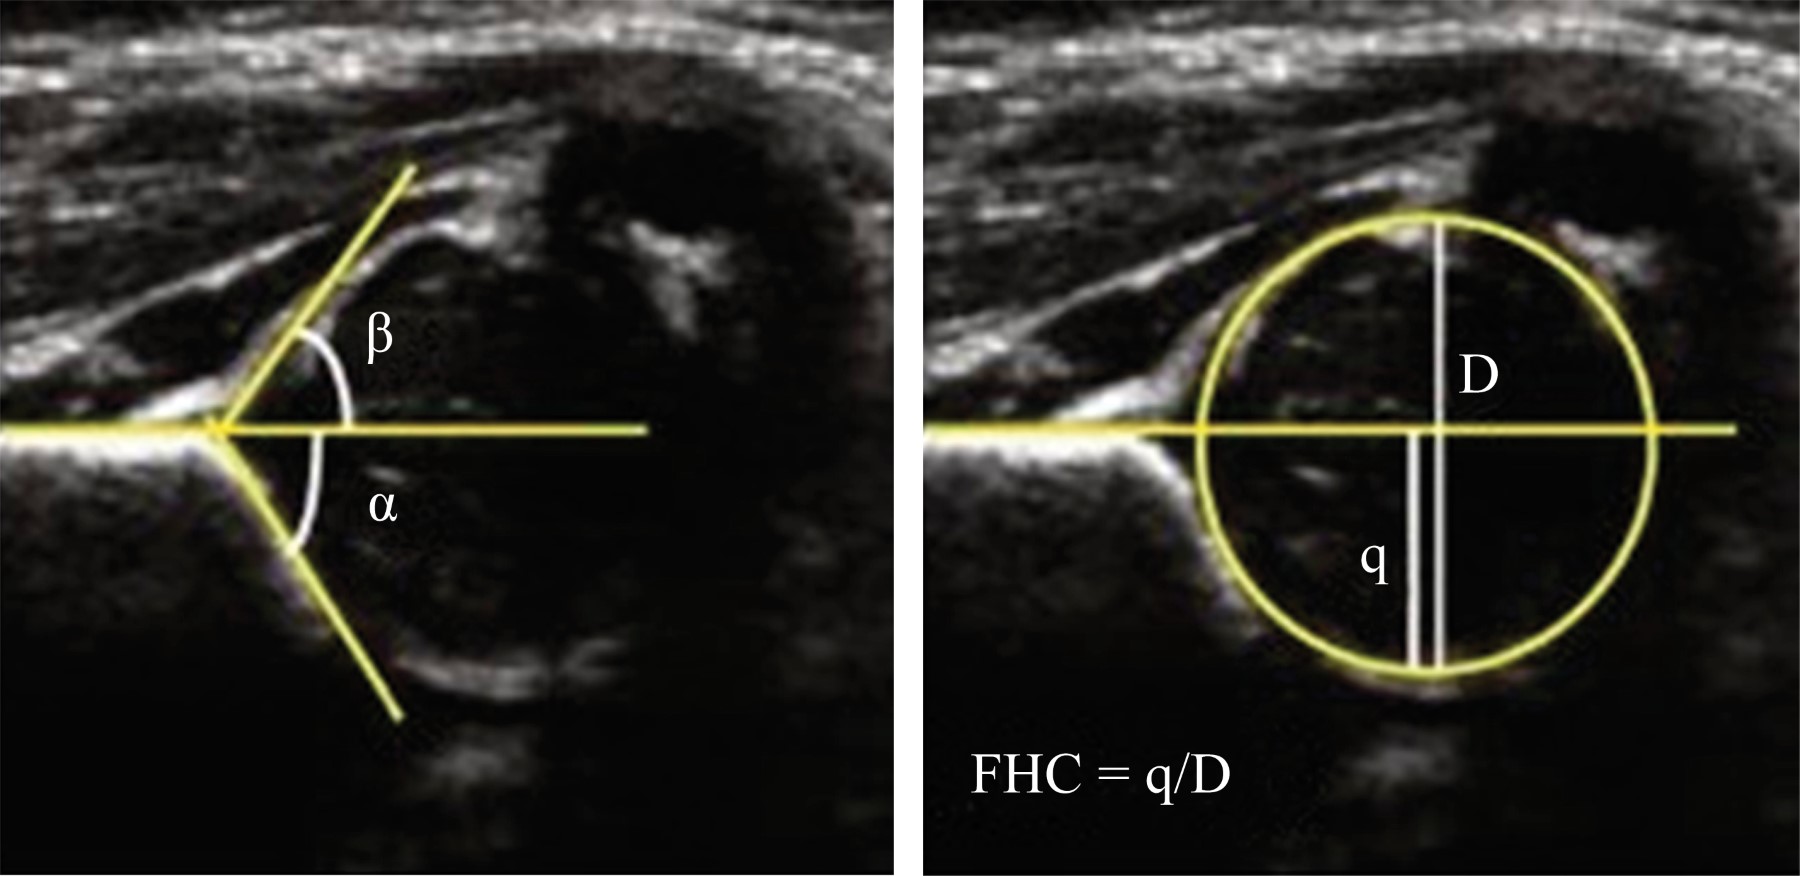

Application of the Graf method for diagnosis and early detection of hip dysplasia

Introduction: Developmental hip dysplasia (DHD) is the most common disorder affecting pediatric hip; screening all neonates clinically, and using ultrasonography selectively for those babies who are at high risk is a widespread recommendation. our goal is to evaluate the impact that USG diagnosis and early treatment of DHD has had on the child population of our unit. Material and methods: Retrospective, descriptive and cross-sectional study. Records of those children from one to six months of age, with a diagnosis of DHD, without distinction of sex, subjected to ultrasonographic tracking in the period from January 2018 to December 2019 were reviewed. A follow-up of six months was carried out in all patients, from the moment of diagnosis and the start of treatment with harness, weekly visits for relocation, as well as ultrasonographic revision every four weeks to monitor the treatment. Results: 19 cases were reported from the left side (47.5%), 10 cases from the right side (25%) and 11 bilateral cases (27.5%). The main associated risk factors were: product of the first pregnancy, family history of DHD, pelvic presentation, female sex. The results were favorable with a continuous use of harness of 23 hours observing a satisfactory evolution in 99.2% of the patients. Conclusion: With the results obtained we can analyze the considerable success rate of the hip clinic of our hospital with the realization of the ultrasound, we find a lower incidence of patients with pain, limitation of function, as well as satisfactory gait patterns.

Figure 5

Figure 6